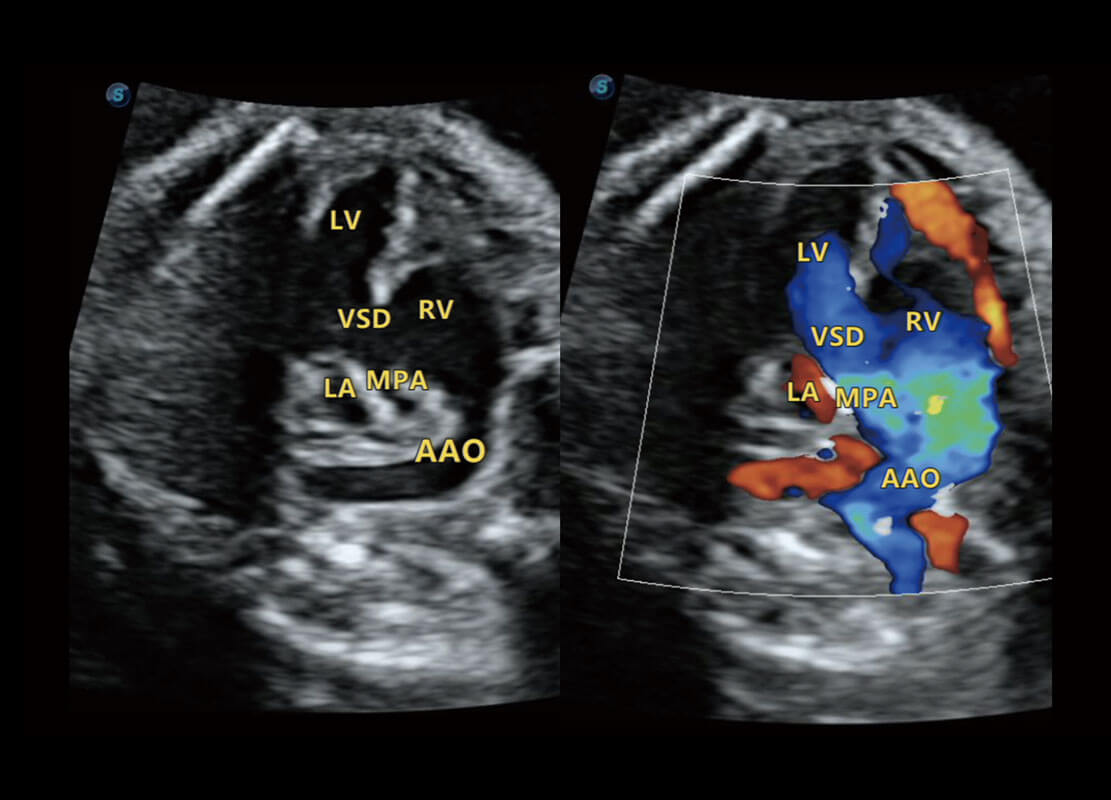

P60搭载一系列胎儿心脏成像技术,实现精细的胎儿心脏评估。

四腔切面

四腔心血流

右室双出口

胎心容积成像